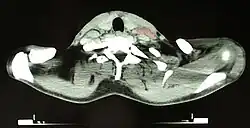

Oberflächlich gelegene Lymphknoten lassen sich mit den Fingern tasten. Für genauere Untersuchungen und die Darstellung tiefer Lymphknoten finden Ultraschall, Computertomografie (CT), Magnetresonanztomografie (MRT), Lymphografie und Szintigrafie (siehe Wächterlymphknoten) Anwendung.

Die anatomische Struktur des Lymphknotens kann im Ultraschall dargestellt werden und zeigt als Normalbefund einen fettigen echoarmen Hilus. Bei unspezifisch reaktiv veränderten Lymphknoten wird dieses Hiluszeichen betont und der Lymphknoten behält seine ovale Form. Ein Fehlen des Hiluszeichens kann auf eine Infiltration durch ein Malignom hinweisen. Sowohl bei reaktiven als auch malignen Lymphknoten kann sich eine Hypervaskularisation zeigen. Ein Verlust der ovalen Form zu Gunsten einer kreisrunden Form des Lymphknotens kann ebenso auf eine Malignominfiltration hinweisen. Nekrosen im Lymphknoten zeigen sich oft echofrei und können sowohl durch abscedierende Infektionen wie auch Einschmelzung einer Tumorabsiedlung entstehen.[7]